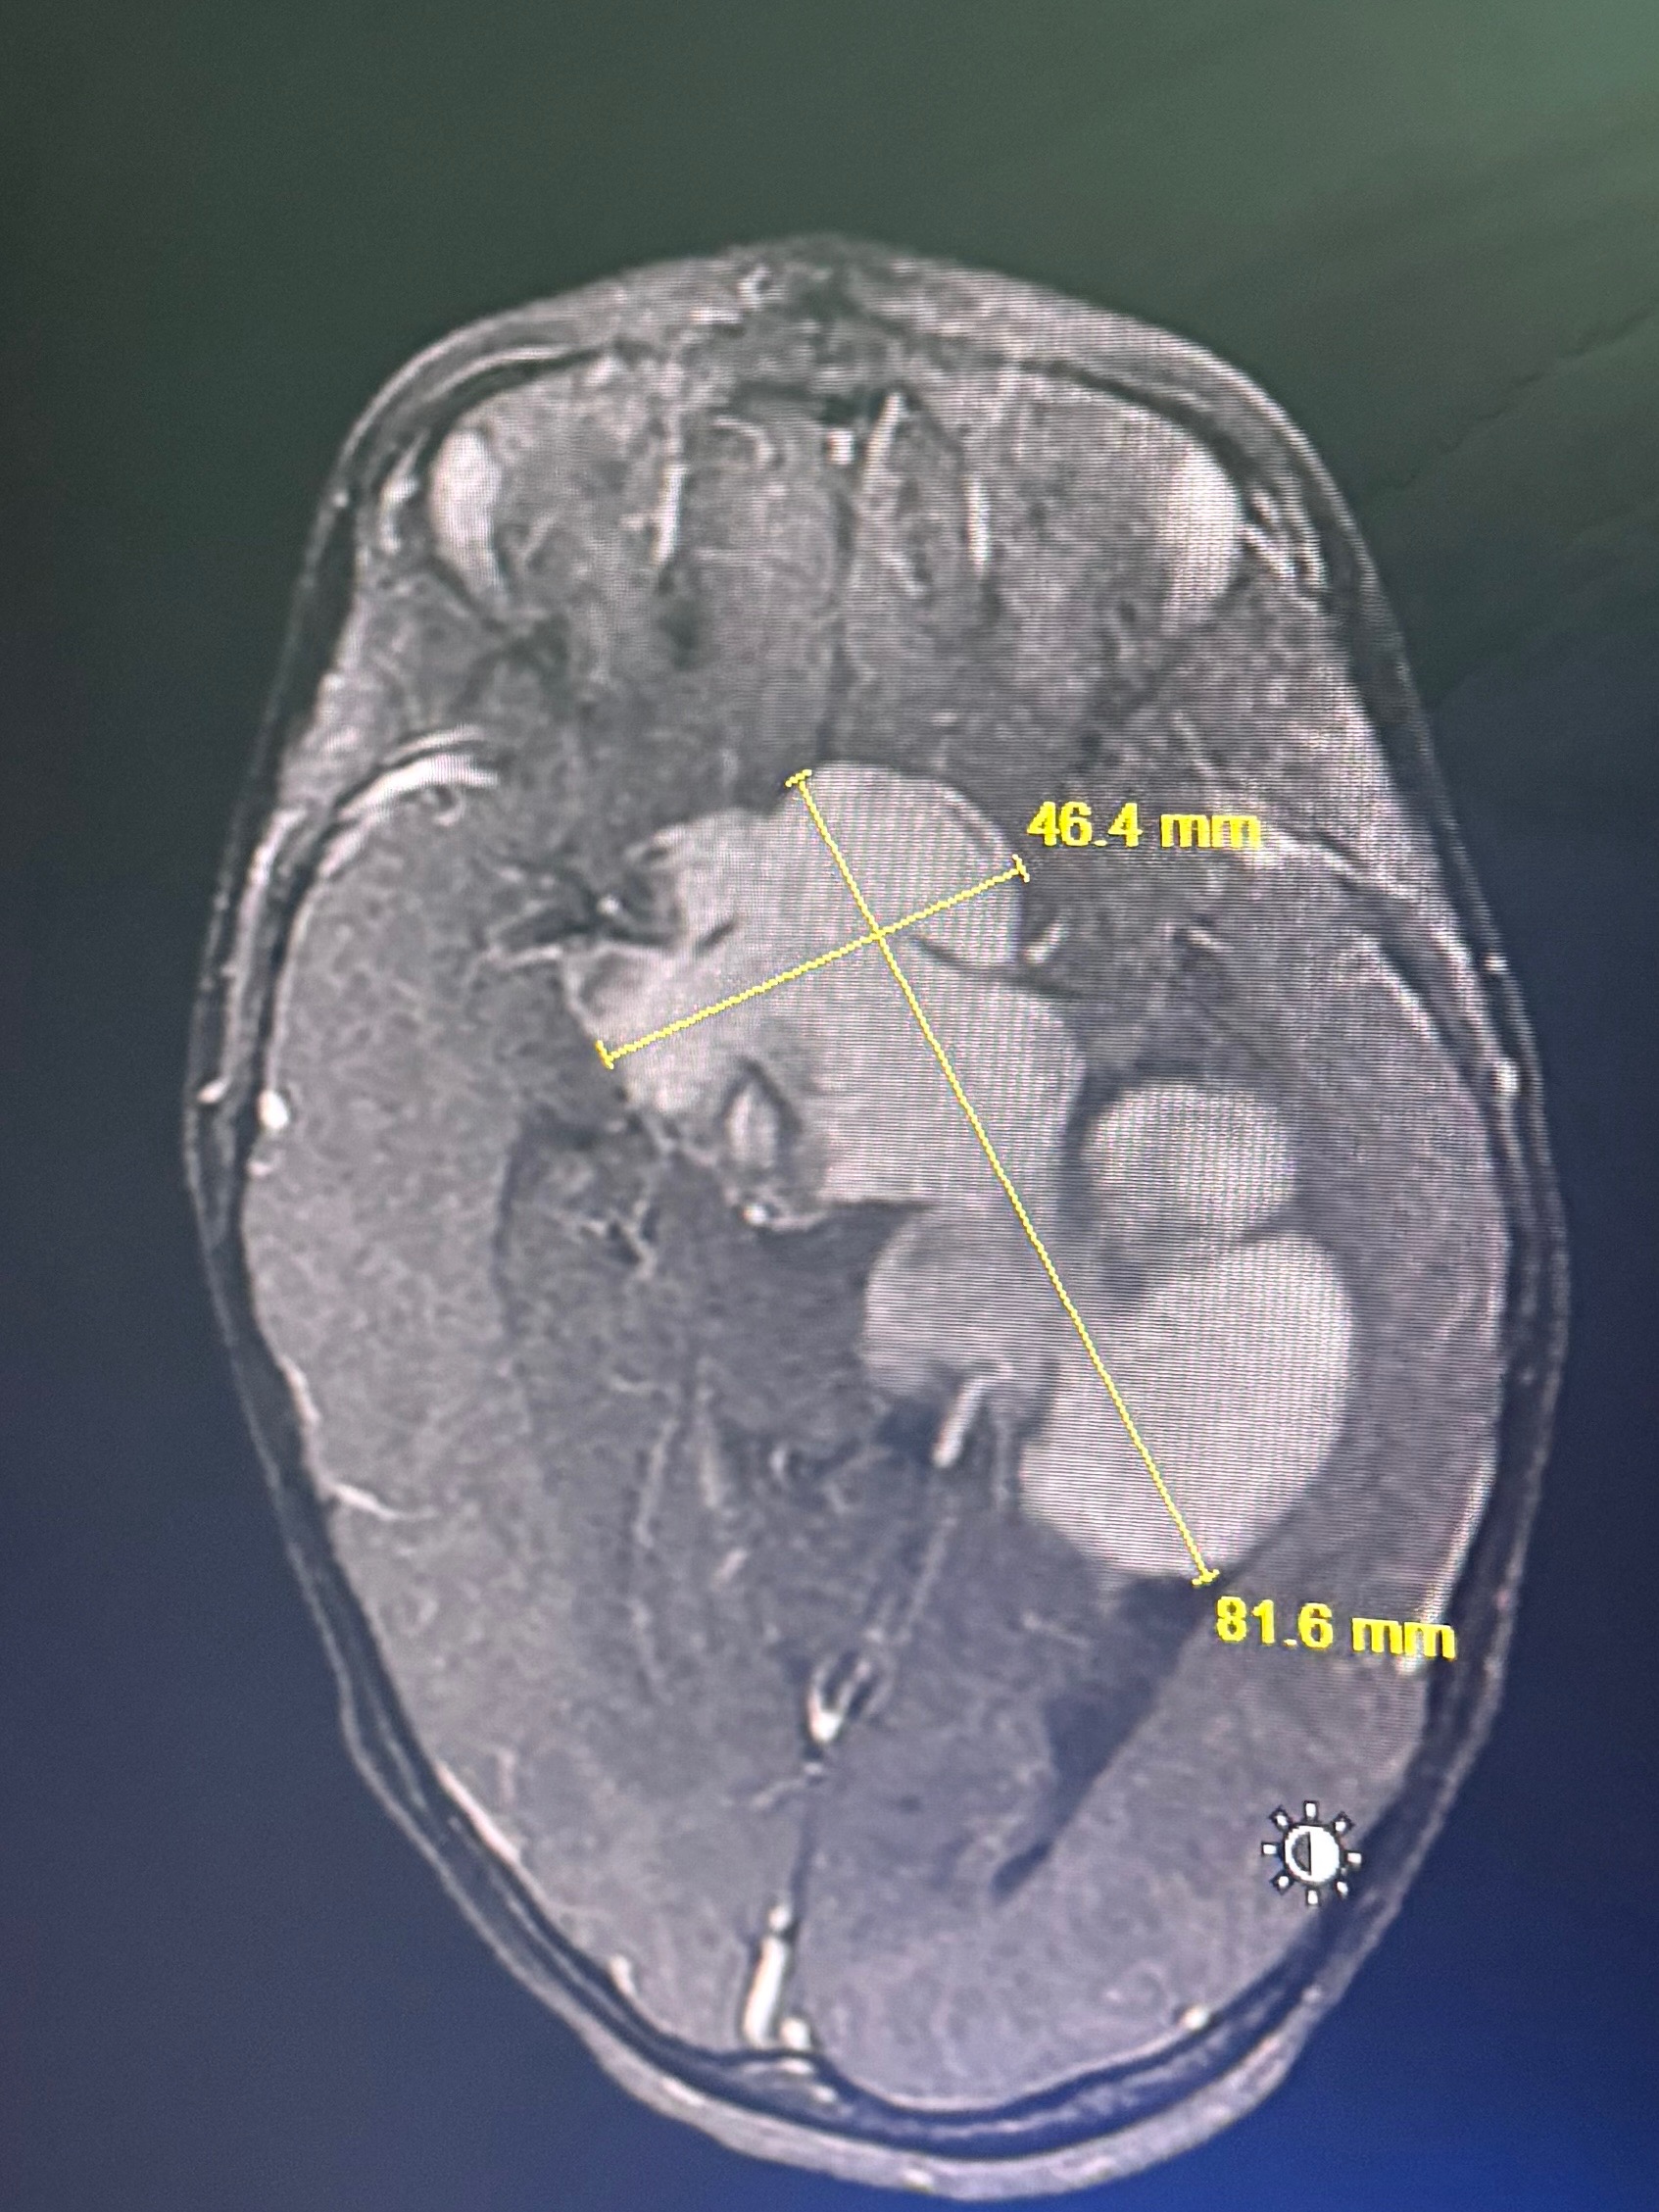

The pair has recently been displaced the week of 04/09/26, one week before Autumn’s first MRI. The pair have attended many evaluations this year to figure out diagnosis and treatment for what appeared to be a neuromuscular weakness on the right side of Autumn’s body, only to find out in the MRI on 04/17 that there is in fact a massive tumor behind her eyes, where the optic nerves cross. Obviously, this unexpected news has blindsided Kat and their extended friends and family in every possible way, and our concern for Autumn cannot be overstated. While it feels deeply uncomfortable to ask for help in this time, they have also struggled with housing largely in silence for 6 months. Autumn deserves better. Not having stable housing is the biggest barrier affecting the course of her treatment as continuity of care is so important, and finding stable housing is essential to Autumn’s well-being.